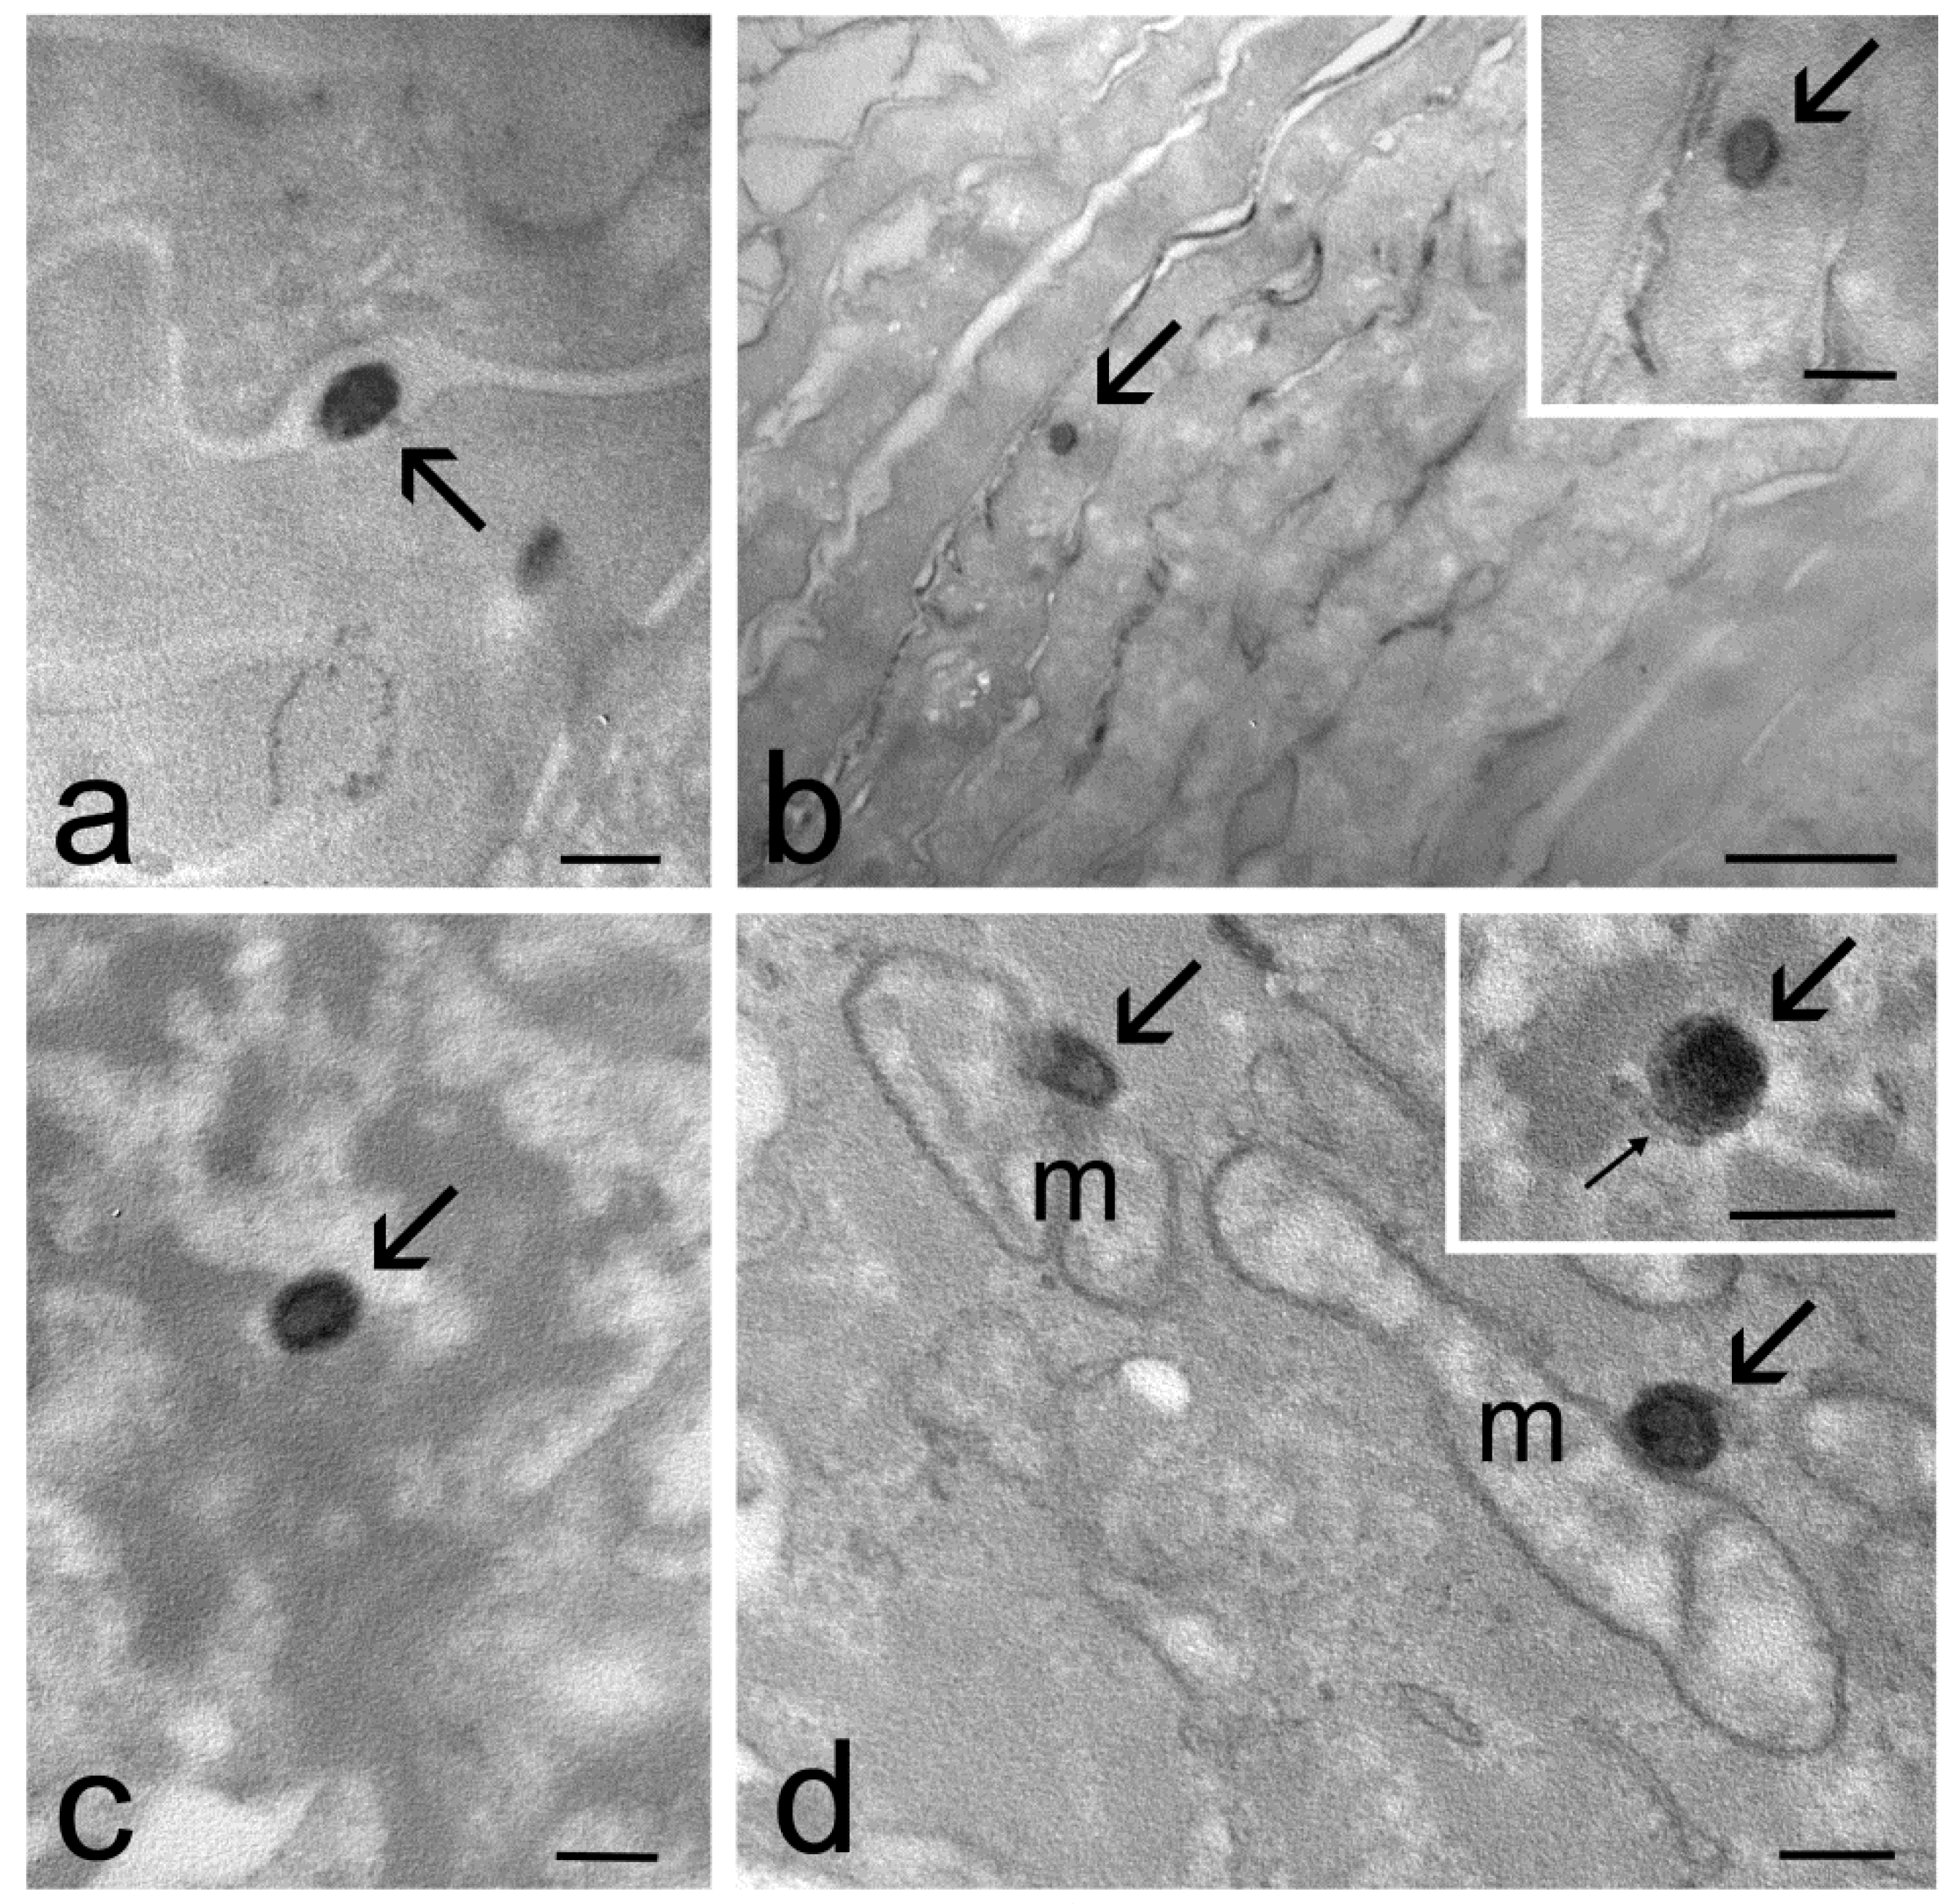

2.4. Transmission Electron Microscopy Study of Skin Penetration

| Skin Strata | ET | TET-1 | TET-2 |

| Stratum corneum | yes | yes | yes |

| Keratinocytes | yes | yes | no |

| Dermis | yes | no | no |